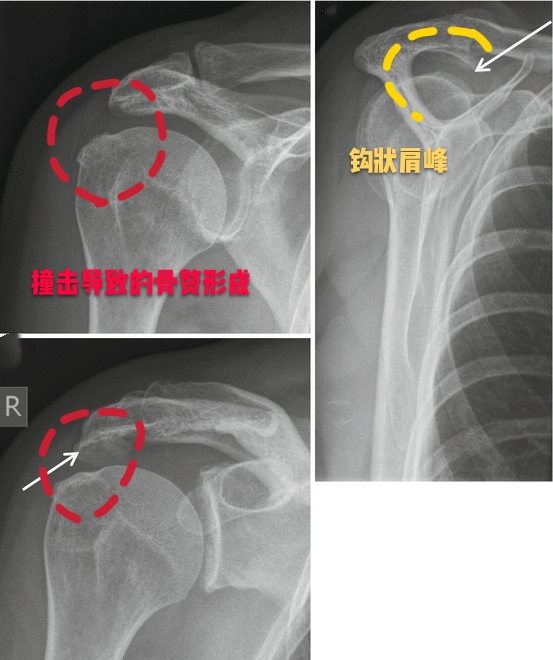

这个房檐形态不是特别的一样,每一个人都有各自的肩峰形态,一般情况下我们的肩峰形态有三种,1种是平的,第2种是略弯曲的,第3种就是钩状的,现在也有人发现有一些人的肩峰是向上翘的,但是这种肩峰不会诱发特殊的症状。主要会导致我们出现肩痛的问题,是三型肩峰,也就是钩状的肩峰,因为向下呈钩状的肩峰,在我们的肩关节活动过程当中,导致肩关节间隙的狭小,会在肩关节活动的过程当中导致撞击!尤其是肩关节做一些前屈、外展、上举的动作时,比如抬起胳膊够比较高的东西,比如羽毛球的挥拍动作。

通常情况下进行肩关节的x线检查或者是核磁检查,可以帮助我们明确肩关节是否存在着肩峰形态的异常以及撞击。

但如果患者经过了保守治疗以后症状仍然特别严重,有可能要进行肩关节镜手术治疗,将钩状的肩峰削平,去除撞击的因素,患者的症状也就会消失了。

对于这样来医院比较急的肩痛患者,往往要首先考虑是否存在着钙化性冈上肌腱炎,要首先给予患者进行最简单的肩关节普通x线平片检查,费用比较低,而且出片比较快,要首先判断是否存在肩关节周边的钙化。